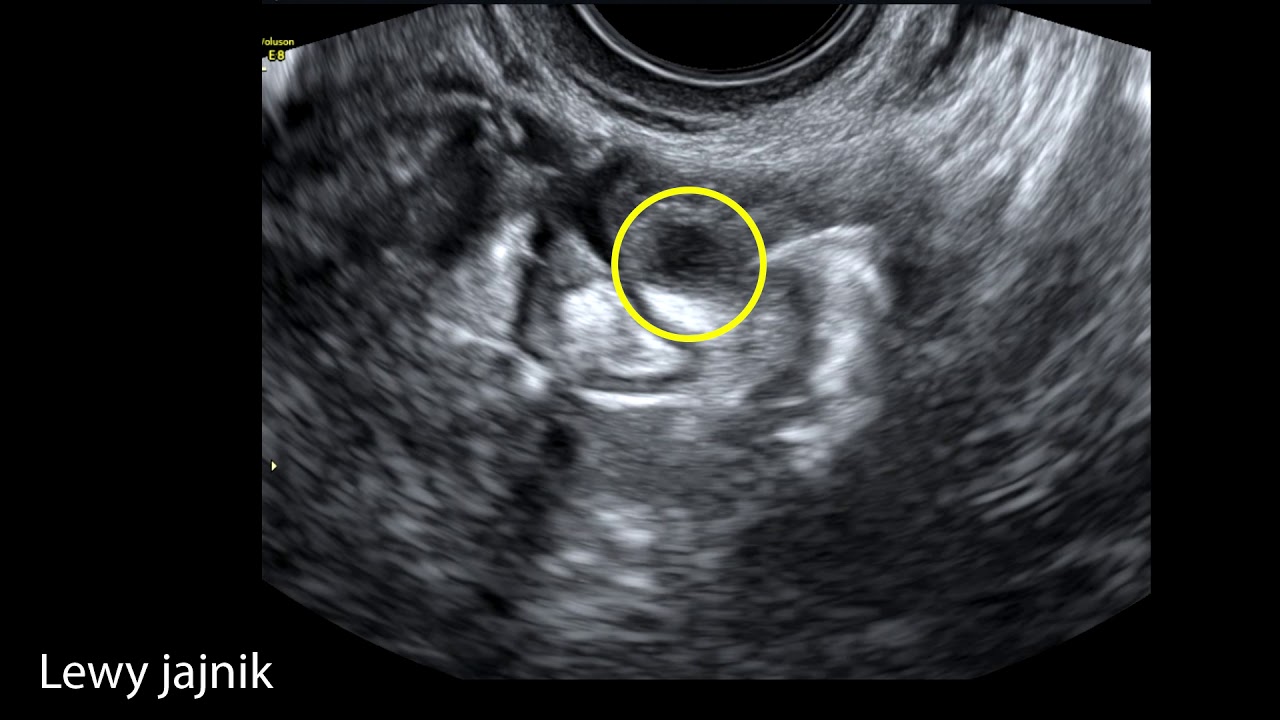

Nowe ciekawe zdjęcie poszerzonego jajowodu z ciążą pozamaciczną 7,2 tyg.

Dodałem zdjęcie jajowodu, który ładnie się ostatnio pokazał podczas wykonywania zabiegu sprawdzenia drożności jajowdów. Drugie zdjęcie to wczesna ciąza w macicy przegrodzonej.

W PARKOWEJ USG wykonuję na aparacie Voluson E8 w najlepszej wersji EXPERT. Istnieje możliwość wykonania badania w rewolucyjnej technice HDlive. Każde badanie nagrywam na pamięć przenośną typu PENDRIVE, które później można wgrać np. do smartfona. Nie nagrywam badań na płytach DVD.